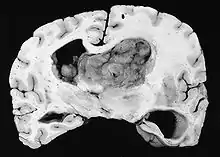

Subependymal giant cell astrocytoma (SEGA, SGCA, or SGCT) is a low-grade astrocytic brain tumor (astrocytoma) that arises within the ventricles of the brain.[1] It is most commonly associated with tuberous sclerosis complex (TSC). Although it is a low-grade tumor, its location can potentially obstruct the ventricles and lead to hydrocephalus.

A NIH Consensus Conference report in 1999 recommends that any SEGA that is growing or causing symptoms should be surgically removed.[2] Tumors are also removed in cases where a patient is suffering from a high seizure burden.[1] If a tumor is rapidly growing or causing symptoms of hydrocephalus, deferring surgery may lead to vision loss, need for ventricular shunt, and ultimately death. Total removal of the tumor is curative.

After complete surgical removal, a SEGA tumor does not grow back. They do not metastasize to other parts of the body. However, the patient is still at risk for, and often develops, new tumors arising from subependymal nodules elsewhere in the ventricular system.